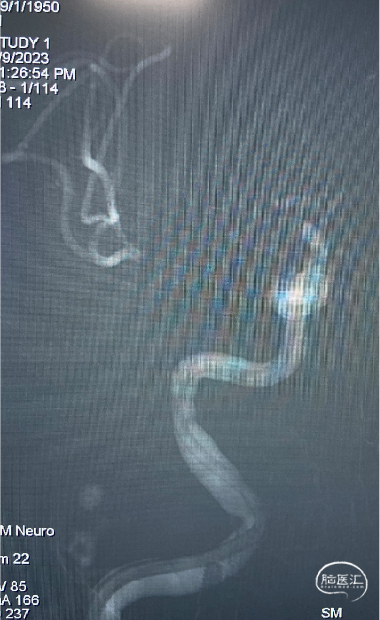

头颈CTA:右侧颈内动脉闭塞,请结合临床。

入院头颅CTA:右颈内闭塞。

右侧颈内动脉闭塞:

第一把:微导丝到位、但Guiding无法越过C1的弯,中间管不能接触血栓。

支架顺利释放,但锚定力度不够。

第二把:微导管显影与第一次不同。重复大脑中动脉?M2上干?仍未通。

果断改经右肱动脉入路,长泥鳅辅助Guiding上高,微导管到位。

A1显影,考虑为T型血栓,且有两条大脑中动脉。

第三组Mark点打开不满意,考虑为支架-血栓交互征,等待8分钟后缓慢张开。

顺利再通!重复大脑中动脉+十字路口的血栓。

回头对比看:重复大脑中动脉的认识,两次微导管进入不同的血管。